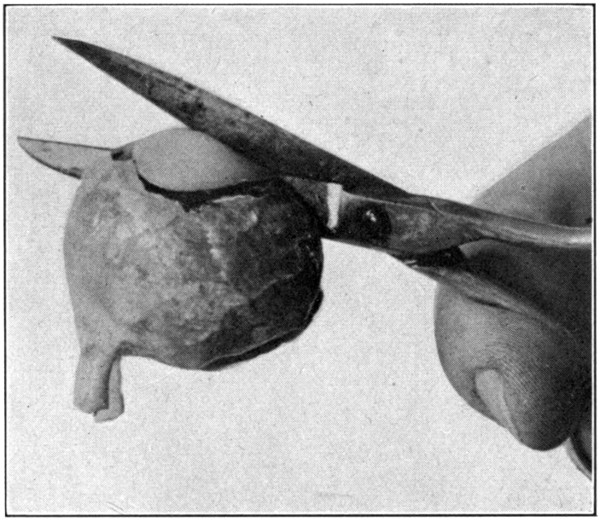

Fig. 2—Making the first cut. (Page 27.)

Fig. 3—Showing how the point of the lower jaw of the scissors is to be kept away from the underlying tissues. (Page 27.)

Fig. 4—Showing about half of the sclerotic separated. (Page 29.)

With a pair of dissecting forceps pinch up

the sclerotic about 5 mm. anterior to the equator.

With a pair of small, fine-pointed scissors,

make an incision. (Fig. 2.) Next hold the

eye in the left hand without exerting any pressure.

Insert the point of the scissors into the

incision which has been made, and cut. Be

careful to keep the point of the scissors close

to the sclerotic or an untimely puncturing of

the choroid will occur. (Fig. 3.) Continue

the[28-

29]

cutting on a line parallel to the equatorial meridian

and about 5 mm. anterior to it until

about half the sclerotic has been separated.

In cutting, always move the point of the scissors

forward with a slight oscillating lateral

movement. (Fig. 4.) While doing this, partly

suspend the eyeball from the point of the scissors.